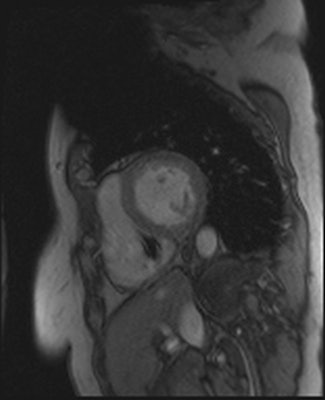

The mean age of the patients was 67 ± 14 years, and 42% (27/64) were women. Altogether 21 (31%) of the examinations were scans of the thorax area, and 20 (29%), 17 (25%), and 16 (24%) of the examinations were MRI scans of spine, head, and heart respectively. The remainder was scans of the pelvis, liver, vagina, rectum, wrist, lung, carotid artery, and soft tissue of the neck, pancreas, and knee.

One of the authors (Sami Pakarinen, HUS Department of Cardiology, Helsinki University Central Hospital) declared a conflict of interest, having been a consultant for St. Jude Medical, Medtronic, Boston Scientific and Biotronik.